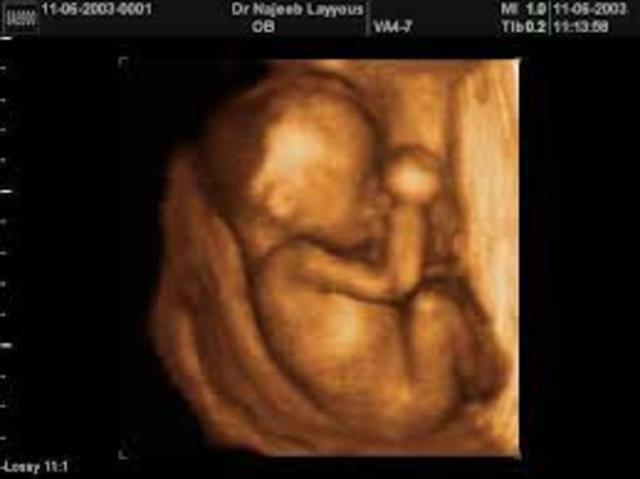

• Pregnancy at 7 & 8 weeks

Pregnancy at 7 & 8 weeks

The baby's brain cells are multiplying. Ears are taking shape, it now has joints in its elbows, wrists, and knees. Your baby will weigh in at a half an ounce. Its major organs are almost complete, the skin is formed but it's transparent, the genitals will start to show but you can't tell whether it's a boy or girl. Your baby is no longer an embryo but is now a fetus. Miscarriages will happen if something went wrong with the development of the embryo, it's usually a genetic or chromosomal defect.